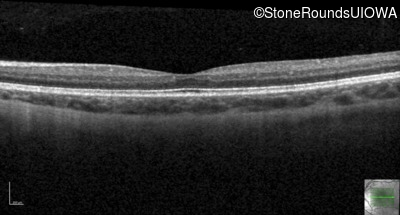

Optical Coherence Tomography - Left - 20/40

Exemplar / OCT Stack